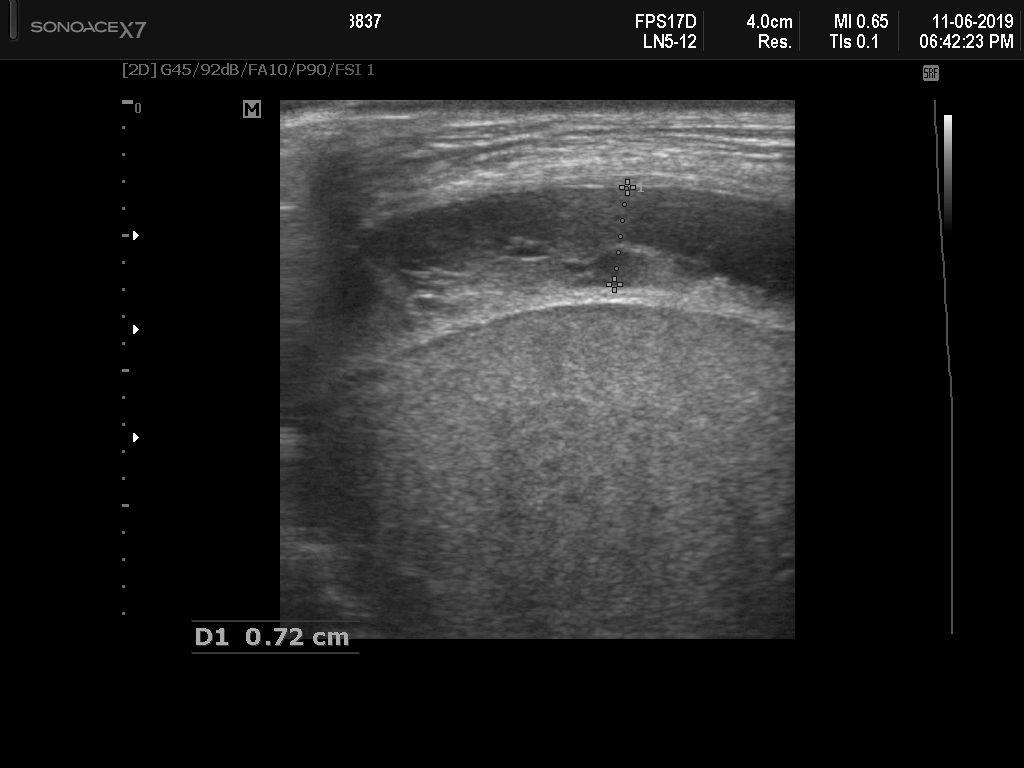

A total of 143 images were acquired from 59 patients. The images were obtained at the left and right PLAPS (PosteroLateral Alveolar and/or Pleural Syndrome) and subcostal views [4] with linear array and curved array (abdominal) ultrasound probes. The data were split according to the use of these probes into two datasets of 51 and 92 images, respectively for linear array and curved array. We denote these datasets as Dataset A (linear array) and Dataset B (curved array). All images were annotated at the time of acquisition to measure the extent of the effusion. These annotations consisted of small crosses at the top and bottom of the deepest area of effusion. See Figure 1 (left column) for example images.

Before being used for training and evaluating the models, each image was automatically cropped using a rectangular/cone mask to remove non-imaging content. Next, we applied an inpainting text algorithm using keras-ocr followed by template matching and edge detection algorithms from opencv to remove the annotations that were added to the images to measure the effusion. Examples of the outputs of this preprocessing are shown in Figure 1 (centre column).

All images in both datasets were manually segmented using the ITK-SNAP software [14] (www.itksnap.org) by a trained observer. Examples of ground truth segmentations are shown in Figure 1 (right column). These segmentations acted as ground truths for training and evaluating the proposed models. Additionally, a second trained observer performed independent segmentations of subsets of 10 random images each from the two datasets. These were used to compute an estimate of inter-observer variability in the manual segmentation process.